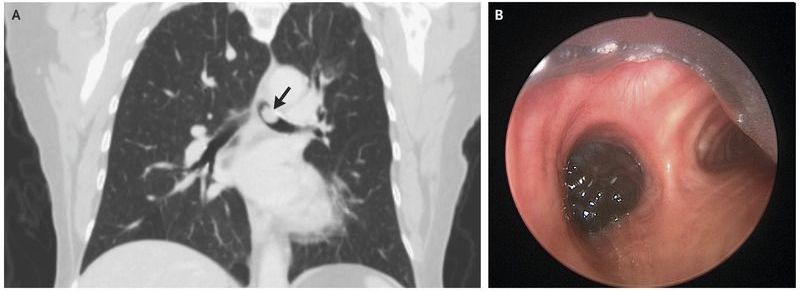

A 70-year-old woman was referred to the pulmonary clinic with a 2-month history of progressive shortness of breath that had been unresponsive to bronchodilators. Three years before presentation, a melanoma had been excised from her left shoulder. The results of lymph-node dissection at that time were negative for metastases. Physical examination was notable for an inspiratory and expiratory wheeze in the left lung. Computed tomography of the chest showed a polypoid lesion that obstructed the left main-stem bronchus (Panel A, arrow). Rigid bronchoscopy revealed a mobile, pigmented mass arising from the bronchus (Panel B ). The mass was débrided with an electrocautery snare and argon plasma coagulation. Pathological examination of the mass confirmed a diagnosis of metastatic melanoma, with BRAF mutation. The patient’s wheezing and shortness of breath completely resolved after the tumor was excised. Treatment of the melanoma with trametinib and dabrafenib was initiated.